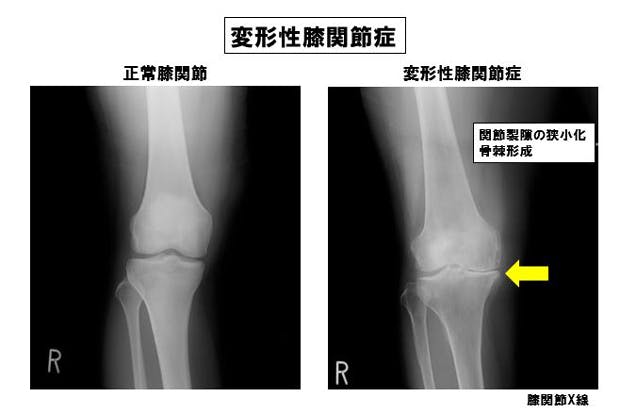

当院にも膝の痛みで受診される患者さんは沢山いらっしゃいます。変形性膝関節症というのは老化して軟骨が磨り減ってきた結果起こす障害です。今まで鎮痛剤の内服やヒアルロン酸関節注射・装具治療・リハビリなどの対症療法が主体でした。

この回旋運動が体重負荷を分散させるのに重要な役割を担っていますが、変形性膝関節症がはじまると回旋運動が消失してきます。すると膝関節への負荷が増大し、変形性膝関節症がどんどん進んでいくわけです。

膝が悪くなる代表的な病気の変形性膝関節症(膝の軟骨がすり減ることによっておこる膝の障害)は、高齢者に多く、女性で60歳代で40%、70歳代で60%、

80歳代で80%にのぼり、その約30%が歩くときに痛みを感じています。